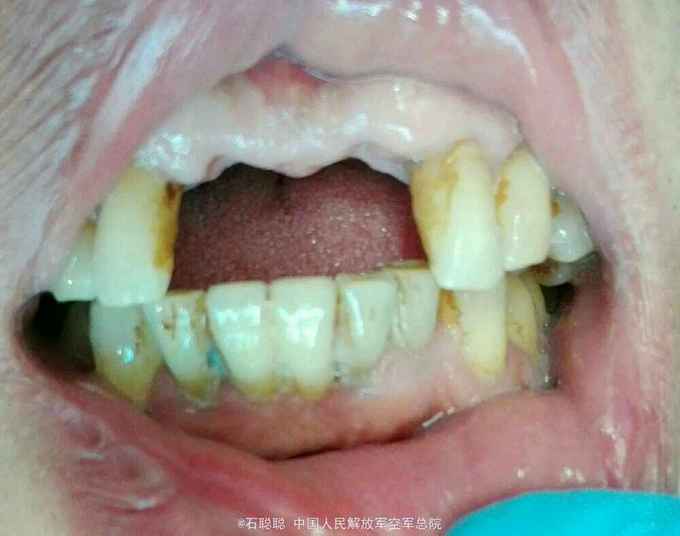

检查:11、21缺失,弹性义齿修复,牙槽脊欠丰满,12、22松动1度,13、23无松动,12、13、22、23未见明显龋坏 根尖片:12、22牙槽骨轻度水平吸收,13、23牙周膜及根尖未见明显异常

诊断:11、21缺失 治疗计划:向患者交代种植、活动、固定义齿修复方案的优缺点,患者考虑到种植周期长、活动修复难以满足美观要求,选择全瓷固定桥修复方案,但患者12、22基牙条件不甚理想,交代患者修复后要严密观察,定期复诊。 处置:12、13、22、23碧蓝局麻下开髓,拔髓,冲洗,置失活剂,氧化锌暂封 一周后复诊:去除暂封,测量根长,12=22=19mm,扩大至25#,13=23=24mm,扩大至35#,大量冲洗,干燥根管,置CP棉球,氧化锌暂封。 一周复诊:12、13、22、23去除暂封,试主尖,冲洗,干燥,冷测压充填,拍摄根尖片,恰填,置干棉球,氧化锌暂封 一周后复诊:12、13、22、23无不适,去除暂封,磷酸锌垫底,树脂充填,预备牙体,排龈,聚醚取模制作临时冠,调磨粘固 一周后复诊:试戴内冠,就位顺利,边缘密合 一周复诊:试戴全瓷桥,由于边缘密合,固位良好,调节正中咬合、前伸咬合、侧方咬合为轻接触,磨光U200粘固